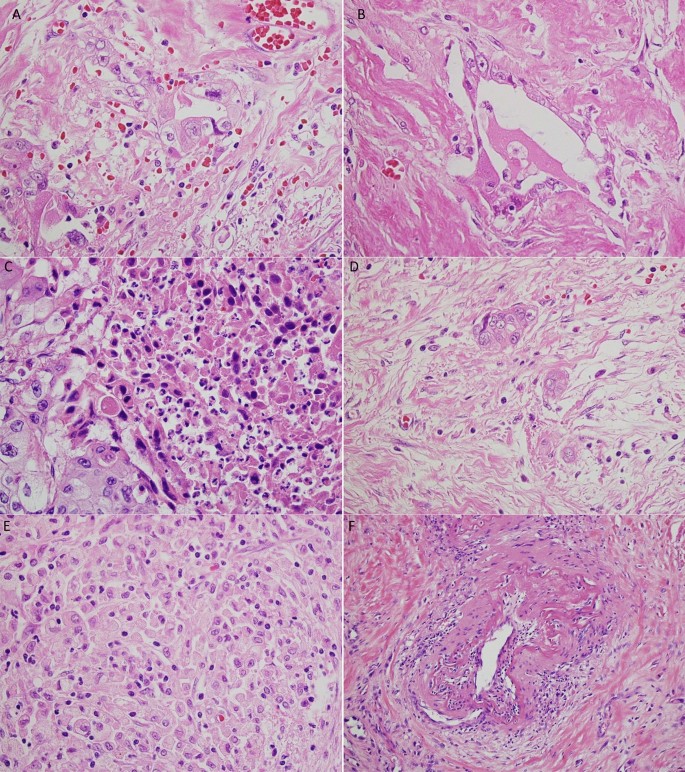

PDAC following NAC often showed the degeneration (Fig. 1A,B) and necrosis (Fig. 1C) of cancer cells. In this study, we defined non-viable tumor cells as those exhibiting pyknosis, karyorrhexis, karyolysis, or the disappearance of nuclei. If it was difficult to distinguish non-viable cells secondary to treatment from degenerative tumor cells secondary to cancer-related ischemic changes, we did not consider those as non-viable cells to avoid overestimating the treatment effects. As for the assessment of fibrosis, we simply evaluated a ratio of the residual tumor cells over the fibrous stroma for the CAP and JPS grading systems, as it was difficult to differentiate fibrosis secondary to NAC from pre-existing or cancer-related chronic pancreatitis. When a few tumor cells were scattered in the fibrous stroma, it was considered a moderate response based on the fraction of the residual tumor (Fig. 1D). Macrophage aggregates without cancer cells (Fig. 1E), vascular degeneration (Fig. 1F), and acellular mucous pools were also considered treatment effects, and we estimated the total tumor mass before NAC including the areas with those lesions in each case.

Histologic changes after neoadjuvant treatment for pancreatic ductal adenocarcinoma (PDAC). (A) Degenerative cancer cells and inflammatory cell infiltration. (B) Degenerative cancer cells in the fibrous tissue. (C) Necrotic cancer cells. (D) A few cancer cells in the fibrous tissue (major response). (E) Macrophage infiltration without cancer cells. (F) Degeneration of a vessel.